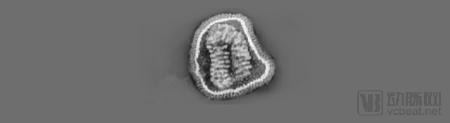

图片2.png

流感病毒颗粒的投射电子显微成像(来源于《流感预测新时代》)